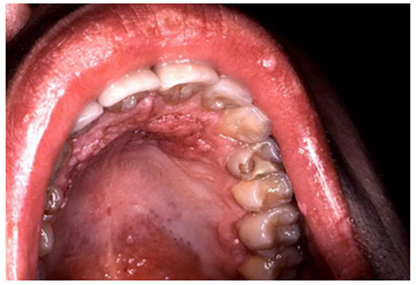

2.png

當(dāng)口腔變成白色、褐色或黑色,尤其是口腔黏膜變粗糙、變厚或呈硬結(jié),意味著黏膜表皮細(xì)胞發(fā)生了變化。出現(xiàn)口腔黏膜白斑、紅斑時(shí),很可能意味著口腔細(xì)胞已發(fā)生癌變。